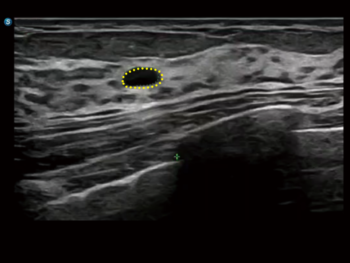

S-Thyroid

Цогц шийдэл бүхий дэвшилтэт хэрэгсэл бөгөөд ACR TI-RADS зааврын дагуу сэжигтэй бамбай булчирхайн бүтцийг илрүүлж, ангилахад тусалдаг. Энэ систем нь шарх болон зангилааны хил хязгаарыг автоматаар тодорхойлж, үзлэгийн дараах тайланг бэлтгэдэг.